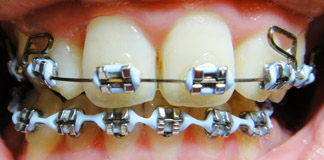

昨天上下排都換了線(上排已經2個月沒換了),這次進度似乎有大躍進~

不過這次調整完還沒踏出門口就覺得整口牙都好痛喔!!!

一樣有亂牙照~~

慎入!!